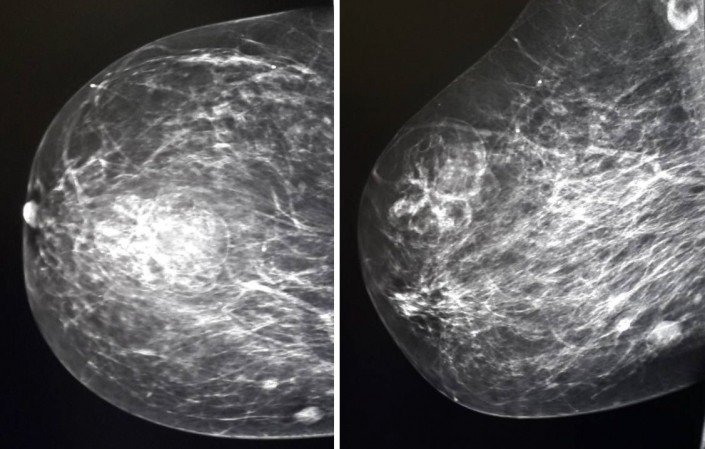

"Первый конкурирующий диагноз, который выставляется пациенткам, - это рак молочной железы или объемное образование, BI-RADS 4", - пишут исследователи.

Во втором случае 50-летняя женщина была направлена на рак правой молочной железы сразу в КазНИИОиР. У нее за пять месяцев до этого была выявлена эхинококковая киста печени, по поводу которой проведено оперативное лечение - резекция печени. Пациентка консультирована маммологом, рекомендовано оперативное лечение.

Как пишут авторы исследования, выявить эхинококкоз в груди помогла информация о наличии этого заболевания ранее. В обоих же случаях болезнь "скрывалась" под видом рака молочной железы. При этом на маммограммах патология не укладывалась в классическую картину патологических состояний (рак, киста, фиброаденома, филлоидная опухоль). Также врачи отмечают, что в обоих случаях образования были безболезненными при пальпации.